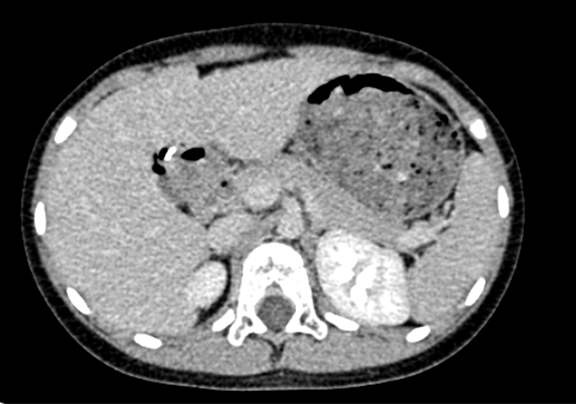

CT: 胆总管囊肿。

上腹部动态增强CT:符合先天性胆管扩张所见(I 型为主)。

术前CT检查:

动脉期

静脉期

平衡期